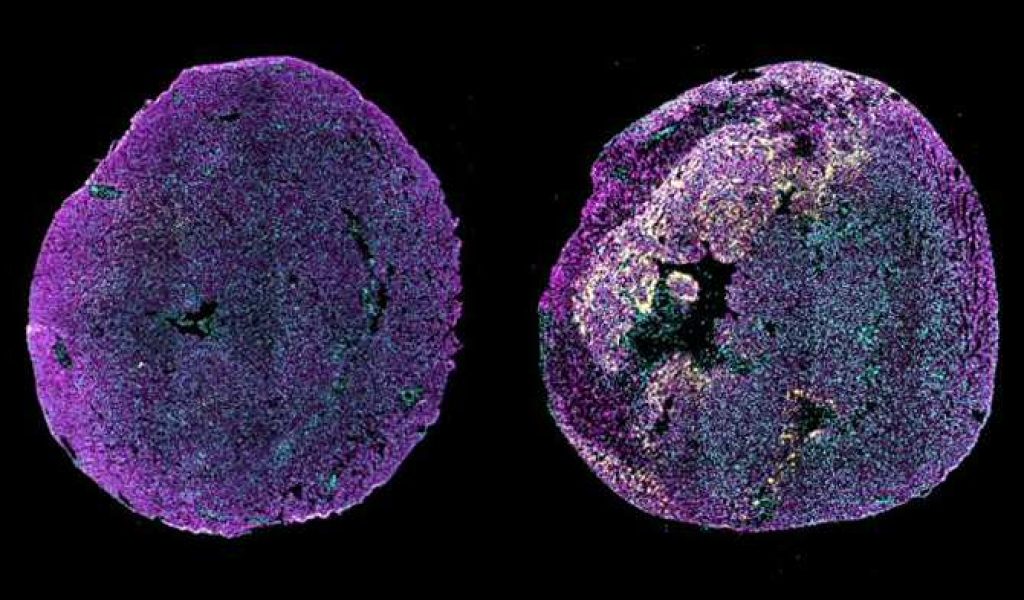

Imagen de inmunofluorescencia de cortes transversales del corazón de un ratón neonatal sano (izquierda) y de un ratón neonatal al que se le indujo un infarto de miocardio en el primer día postnatal, examinado 3 días después de la lesión (derecha). Señalizados en amarillo, aparecen altos niveles de expresión de proANP en la región limítrofe del miocardio lesionado. La proANP es una proteína que responde a las lesiones y que promueve la reparación cardíaca en ratones neonatales. Los cardiomiocitos se muestran en magenta (alfa-actinina) y los núcleos celulares en cian. (Imágenes: Cheng Lab / Columbia University)